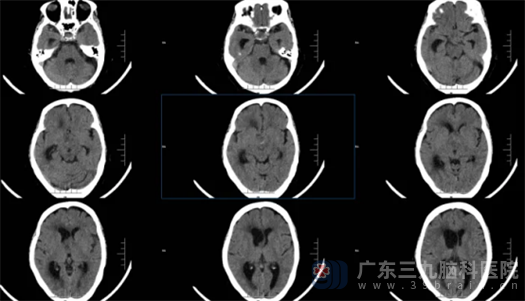

我院副院长鲁明接诊了患者,急诊完善头颅CT检查,结果提示患者鞍区占位、右侧侧脑室脑积水。此时患者已经进入昏迷状态,鲁明迅速组织神经外五科进行讨论,一致同意急诊为患者行右侧脑室外引流术。术后,患者神志清醒,症状明显好转。

术前CT